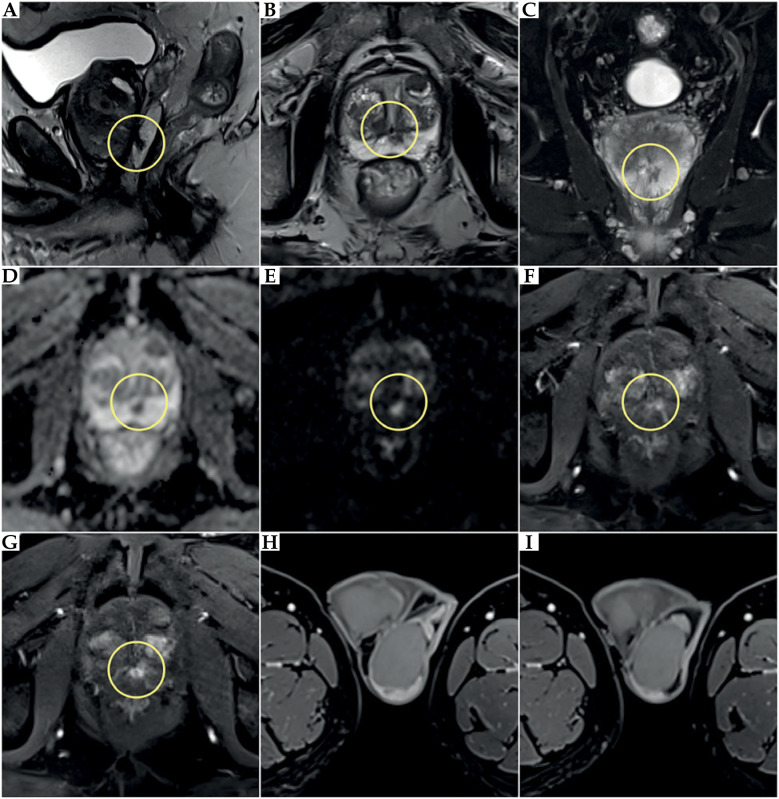

本文的目的是报道一例前列腺癌近距离放射治疗(BT)患者罕见的睾丸附睾炎并发症,该患者在BT治疗4周后行经输尿管前列腺切除术(TURP)。一位73岁的前列腺癌患者(中危组)符合高剂量率(HDR) BT联合雄激素剥夺治疗(ADT) 6个月(leuprorelin)的条件。由于BT术后尿潴留等症状加重,患者需要导尿。此外,下尿路和前列腺存在细菌性炎症。由于排尿障碍延长,行TURP,在BT完成4个月和TURP后拔管3个月后导致慢性睾丸附睾炎。由于长期炎症,治疗无效,切除左睾丸及左附睾。不幸的是,术后在床和左腹股沟出现炎症症状。由于这些不同程度的症状持续存在,因此引入了抗炎药和镇痛药。在HDR-BT后进行TURP过快可能会导致严重的并发症。对于接受BT治疗的患者,应慎用TURP,在BT后发生泌尿系统疾病时,必须采取保守和药物治疗,任何干预(TURP)应在BT后至少3-6个月进行,这一点尤其重要,因为随着时间的推移,辐射效应会逐渐发展。

The aim of this paper was to present a rare complication of orchiepididymitis in a patient treated with brachytherapy (BT) for prostate cancer, who underwent trans-ureteral resection of the prostate (TURP) four weeks after BT. A 73-year-old patient with prostate cancer (intermediate-risk group) was eligible for high-dose-rate (HDR) BT combined with androgen deprivation therapy (ADT) for 6 months (leuprorelin). Due to increased symptoms, such as urinary retention after BT, the patient required catheterization. Additionally, bacterial inflammation in the lower urinary tract and prostate was present. Due to prolonged micturition disorders, TURP was performed, leading to chronic orchiepididymitis four months after completion of BT and three months after catheter removal following TURP. Due to long-term inflammation, which was resistant to treatment, the left testicle with left epididymis was removed. Unfortunately, inflammatory symptoms occurred post-operatively in the bed and the left groin. Since these symptoms of varying severity continued, anti-inflammatory drugs and analgesics were introduced. TURP performed too quickly after HDR-BT might cause severe complications. Extreme caution regarding TURP should be exercised in patients undergoing BT. Conservative and pharmacological treatment must be introduced in the occurrence of urinary disorders after BT, and any intervention (TURP) should be performed at least 3-6 months after BT. This is especially crucial because of the development of radiation effect over time.